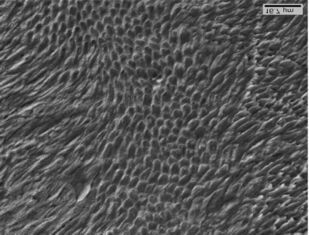

В данном учебном пособии рассмотрены вопросы этиологии, патогенеза, клиники и дифференциальной диагностики клиновидных дефектов зубов, освещены современные подходы к лечению пациентов с клиновидными дефектами твердых тканей зубов, отражена их взаимосвязь с фоновыми заболеваниями организма. В работе представлены научные разработки кафедры ортопедической стоматологии Санкт-Петербургской медицинской академии последипломного образования по изучению морфологического строения и химического состава твердых тканей зубов.